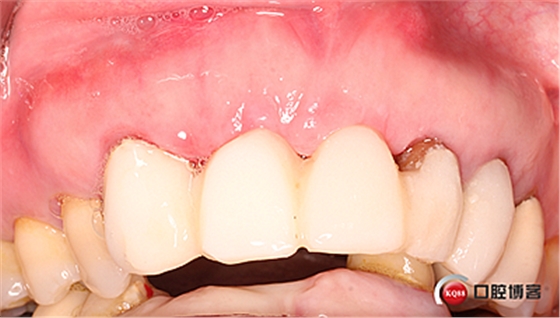

水平切口,鄰牙冠延長。

擴孔,檢查方向。

大家注意這個動作,雖然不翻瓣,但要將唇側(cè)倒凹處骨膜剝離。

植入植體。

將骨粉塞入剝離的骨膜下間隙里既唇側(cè)倒凹處,盡量塞滿。